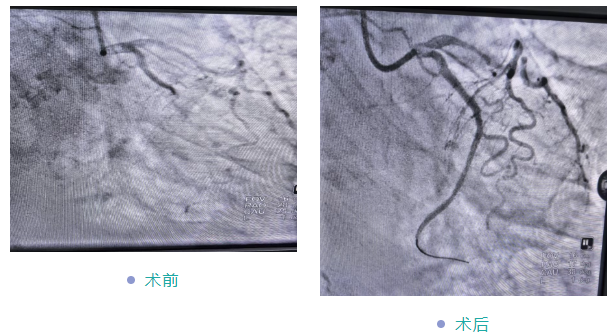

据悉,该患者因“反复胸痛1年,再发加重10天”入院,经初步检查确诊为冠心病。考虑到患者年事已高、身体耐受度有限,传统治疗风险较高,心血管内科团队高度重视,立即组织科内讨论,全面评估其心肺功能、基础疾病及手术风险,经充分研讨后制定了个体化微创介入方案——先通过冠脉造影明确病变情况,再视结果实施支架植入。

手术当日,在副院长黄修平与心血管专科医生李昊弋的精准操作、默契配合下,冠脉造影与支架植入顺利完成,全程平稳有序。术后,患者胸痛症状明显缓解,生命体征稳定;在医护团队的精心照料与个体化康复指导下,次日即可下床行走,精神状态显著改善,目前已康复出院。